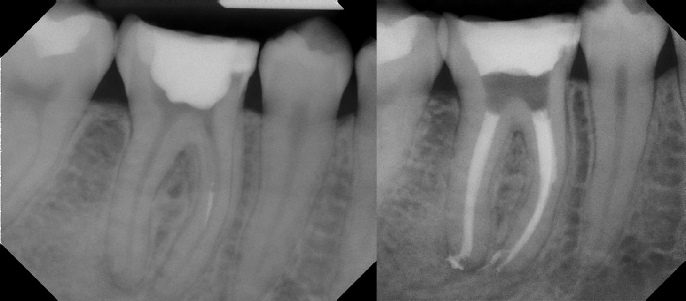

COMPLICATED ANATOMY LARGE LESIONS CALCIFIED CANALS PERFORATION / RESORPTION SEPARATED INSTRUMENTS SURGICAL CASES RETREATMENT / pOST REMOVAL OPEN APICES ACCESS THRU CROWNS Root Canal Case Portfolio

Pre-op Post-op 1 Post-op 2